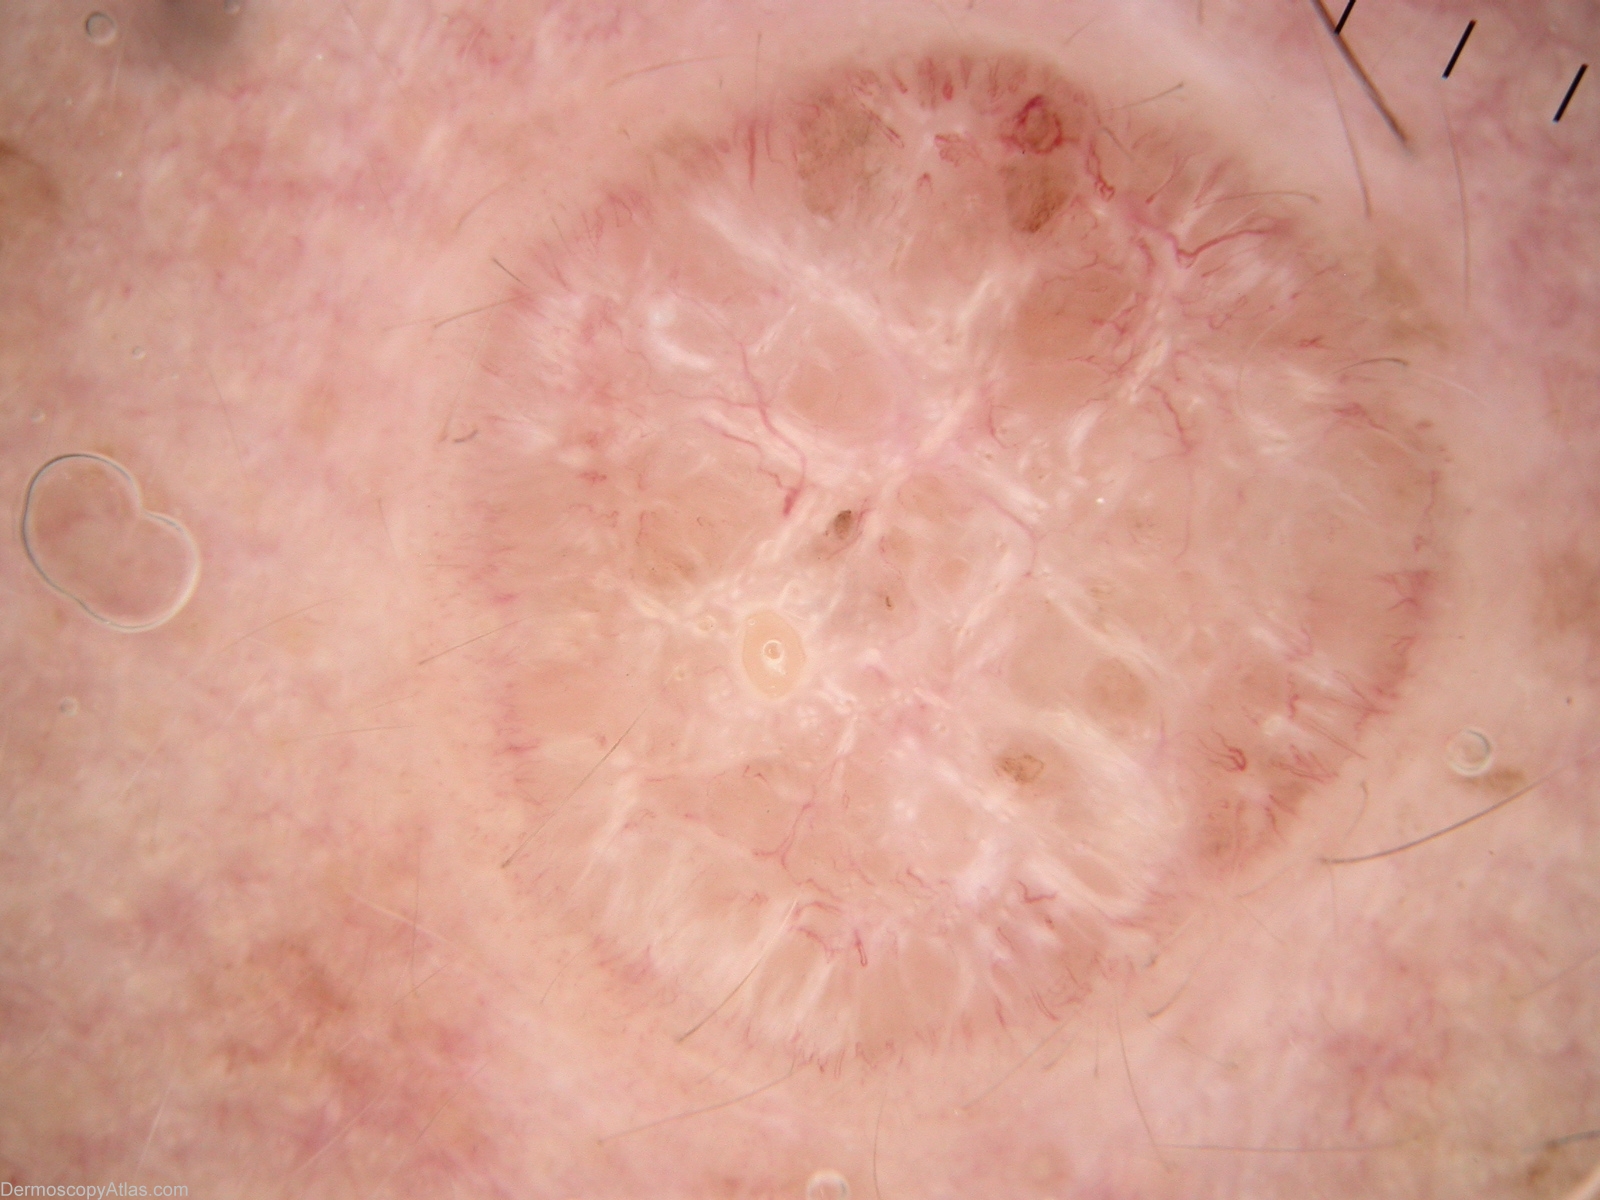

Site: Forehead

Diagnosis: BCC - Solid

Type: Mixed

Submitted By: Alan Cameron

Description: Dermlite Fluid non-polarising. Vessels are concentrated peripherally, either thin hairpin or linear. I cannot convincingly call the lightly pigmented regions either blue/grey ovoid nests or leaf-like areas. While arborising vessels are diagnostic of BCC, BCCs may have many other vessel patterns

History: Slowly enlarging plaque on forehead.